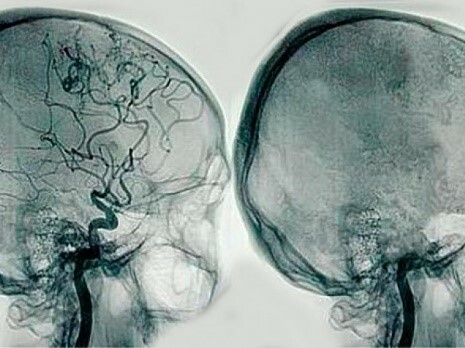

Destacan los avances en microcirugía con el desarrollo del microscopio, la neuroanestesia, instrumentos de coagulación, inicios de neuro-radiología con la ventriculografía y arteriografía, antibioterapia y potenciación del esterotaxia.

introdujo las técnicas de ventriculografía y neumoencefalografía. Realizó y refinó innumerables técnicas quirúrgicas destinadas a la resección de tumores interventriculares describió el uso de los primeros neuroendoscopios, fue el primero en clipar un aneurisma cerebral.